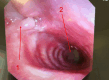

Postpneumonectomy syndrome (PPS) is a rare complication after pneumonectomy characterised by severe mediastinal shift leading to airway compression and respiratory distress. We present a case of a woman in her mid-40s who developed PPS following a right pneumonectomy for bronchial mucoepidermoid carcinoma. Surgical treatment of PPS had not previously been performed in Denmark by Danish surgeons, which is why we consulted with a British surgeon. The surgery was performed in Denmark.The procedure resulted in immediate respiratory improvement, and the patient was discharged 22 days postoperatively. Follow-up demonstrated sustained airway patency and no signs of cancer recurrence. This case highlights the feasibility and effectiveness of surgical management of PPS in centres with limited prior experience and supports mediastinal repositioning with prosthetic implants as a viable treatment option in severe cases.